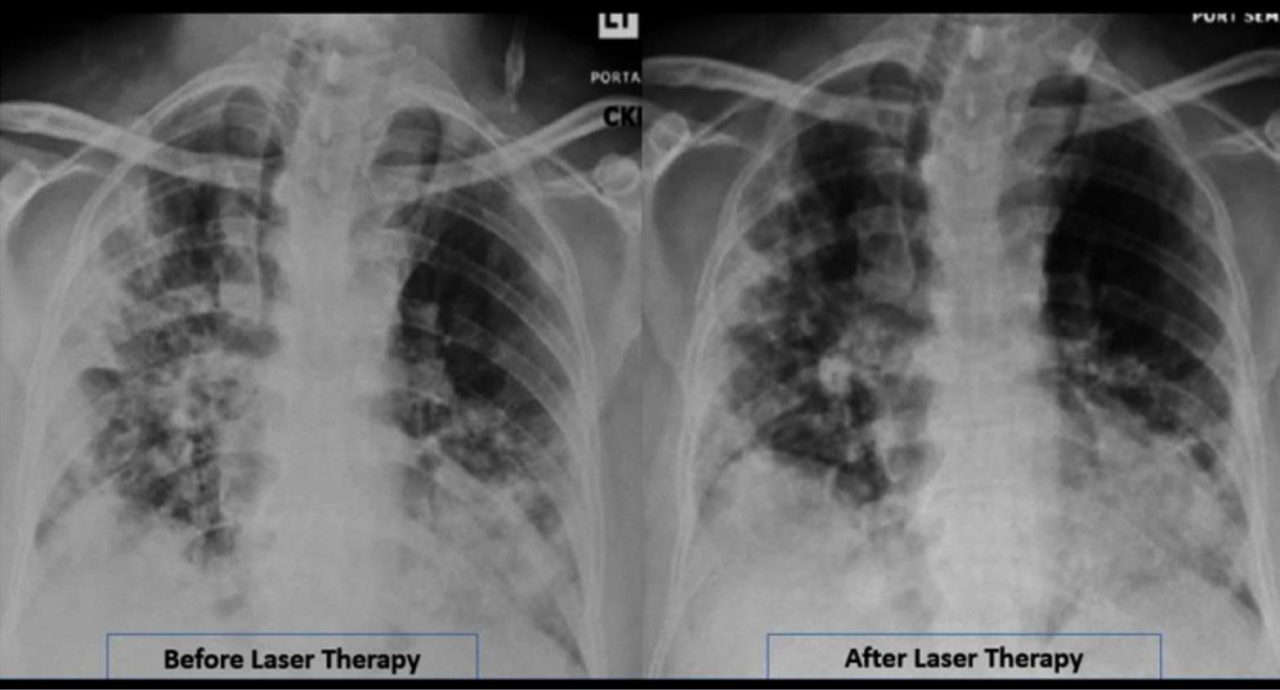

MLS laser preukázateľne zmierňuje zápal a má regeneračné účinky, čo sa dá potvrdiť aj diagnostikou na RTG. Prvé poznatky ukazujú, že je veľmi dôležité aplikovať MLS terapiu čo najskôr, hneď po objavení symptómov, alebo bezprostredne po prekonaní koronavírusového ochorenia.

MLS terapia kombinujúca najnovšie vedecké poznatky z odboru biomedicínskych vied s vysoko pokročilým technologickým riešením stimuluje regeneračné procesy a odstraňuje bolesť, čo sa využíva aj v rehabilitácii a regeneratívnej medicíne. Ide o efektívnu a preukázateľne účinnú terapiu bez nežiaducich vedľajších účinkov. Jedinou dnes známou kontraindikáciou je ošetrenie miesta na tele, kde prebieha rakovinové bujnenie. „Vysoko výkonný MLS laser má výrazný protizápalový účinok, pôsobí na princípe blokády zápalového cytokínu interleukínu-6, ktorý je zodpovedný za imunitnú odpoveď organizmu, tzv. cytokínovú búrku. Je to všeobecná hyperimunitná reakcia na infekčný agens, ale pri koronavírusovej infekcii je táto reakcia veľmi výrazná. Je tiež jedným z hlavných aspektov zhoršenia stavu pacienta s covidovou pneumóniou, kedy sa výrazne zhoršuje zápal v pľúcnom tkanive a aj saturácia kyslíkom. Pri použití MLS laseru dochádza k útlmu cytokínovej búrky, a tým pádom aj k zlepšeniu klinického stavu pacienta.“

Práve zápal môže spôsobiť zlyhanie dýchania a pľúcnych funkcií, čo vedie k nutnosti ventilácie. Navyše je zodpovedný aj za tzv. zjazvenie pľúcneho tkaniva vo fáze hojenia, čo tiež spôsobuje zhoršenie pľúcnych funkcií.